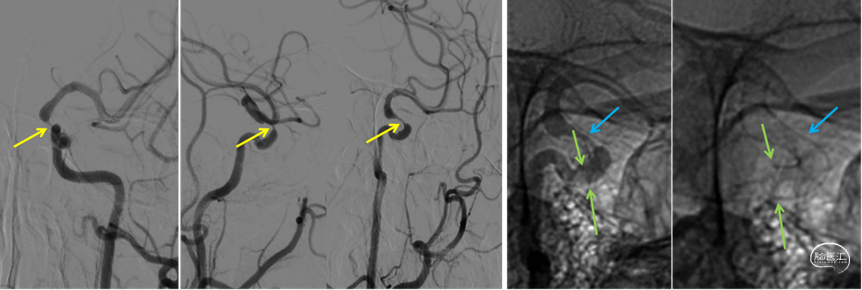

图片.5: 术后工作角度造影及朦片显影,可清楚看到动脉瘤内造影剂明显滞留(黄箭头),支架位置良好,贴壁性佳(绿箭头:支架头端;蓝箭头:支架尾端)